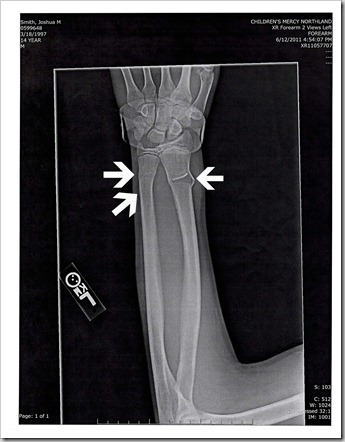

Of course there is always a monkey wrench in the best thought out plans, right? Sunday evening my 14 year old, Joshua, wrecked his bike and broke both bones in his arm in 3 places total. Yes… on a Sunday (don’t things like this always happen on the weekends at your house?). So off to the local children’s hospital urgent care center we went.

Because of the amount of pain he was in, we were able to be seen fairly quickly. Poor Josh could not straighten out his wrist, it was stuck in an arched position and he could barely wiggle his fingers. After some poking and prodding and a few x-rays we began the waiting game. The physician there put in a call to ortho because she wasn’t sure how they would want to procede.

So I am going to try to make a long story short. They splinted him and told us to make an appointment with ortho the next week. The next morning his fingers looked like sausages and he needed to be taken back in. Another visit with a physician, another call into ortho and we were sent to the children’s hospital ER to have his arm reset (it seems that born on the left was curved now and that is why his wrist wouldn’t bend). All of this occurred on Monday. Yes, Monday afternoon & evening… the day the family was to go camping. Our van was packed to the gills, so we drove to the campground to unload and Joshua and I spent the afternoon/evening in the ER together.